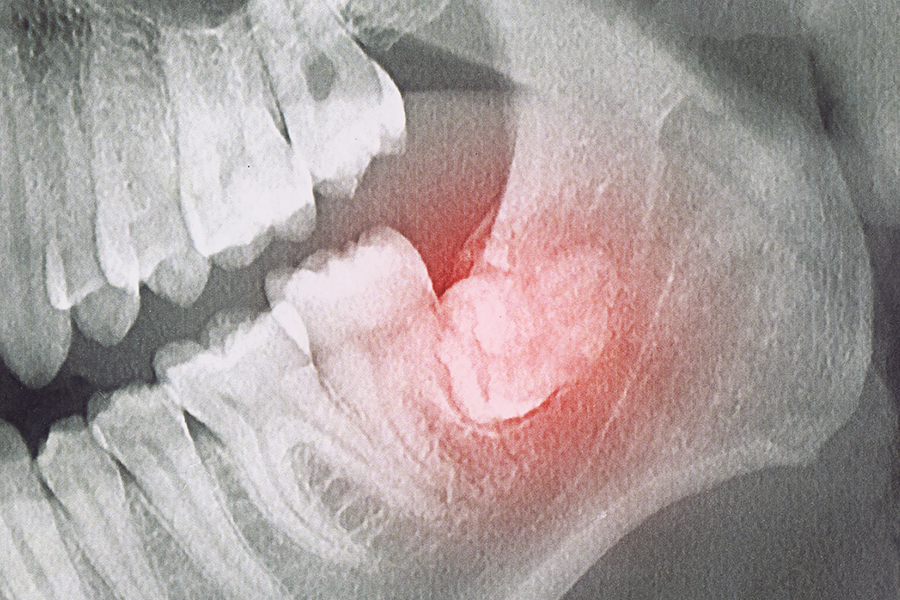

• 04 매복으로 인한 낭종·감염 등 합병증을 조기에 차단합니다.

• 05 X-ray/CT에서 낭종(뼈낭종)·완전 매복이 의심되는 분

뿌리 형태와 위치, 신경·상악동과의 거리를 파악해 안전한 발치 계획을 세웁니다.

음식 끼임·구취가 지속될 때, X-ray/CT에서 낭종이 의심될 때 발치를 고려합니다.